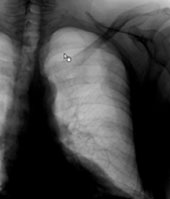

Ein 42-jähriger Freizeitsportler stürzte vor einigen Tagen bei einer Velotour auf die linke Flanke und kommt nun in Ihre Praxis wegen persistierenden thorakalen Schmerzen, v.a. bei tiefer Inspiration.

Sie veranlassen ein Thoraxröntgen, dessen Aufnahmen Sie hier sehen:

Thorax (Ausschnittsaufnahme)